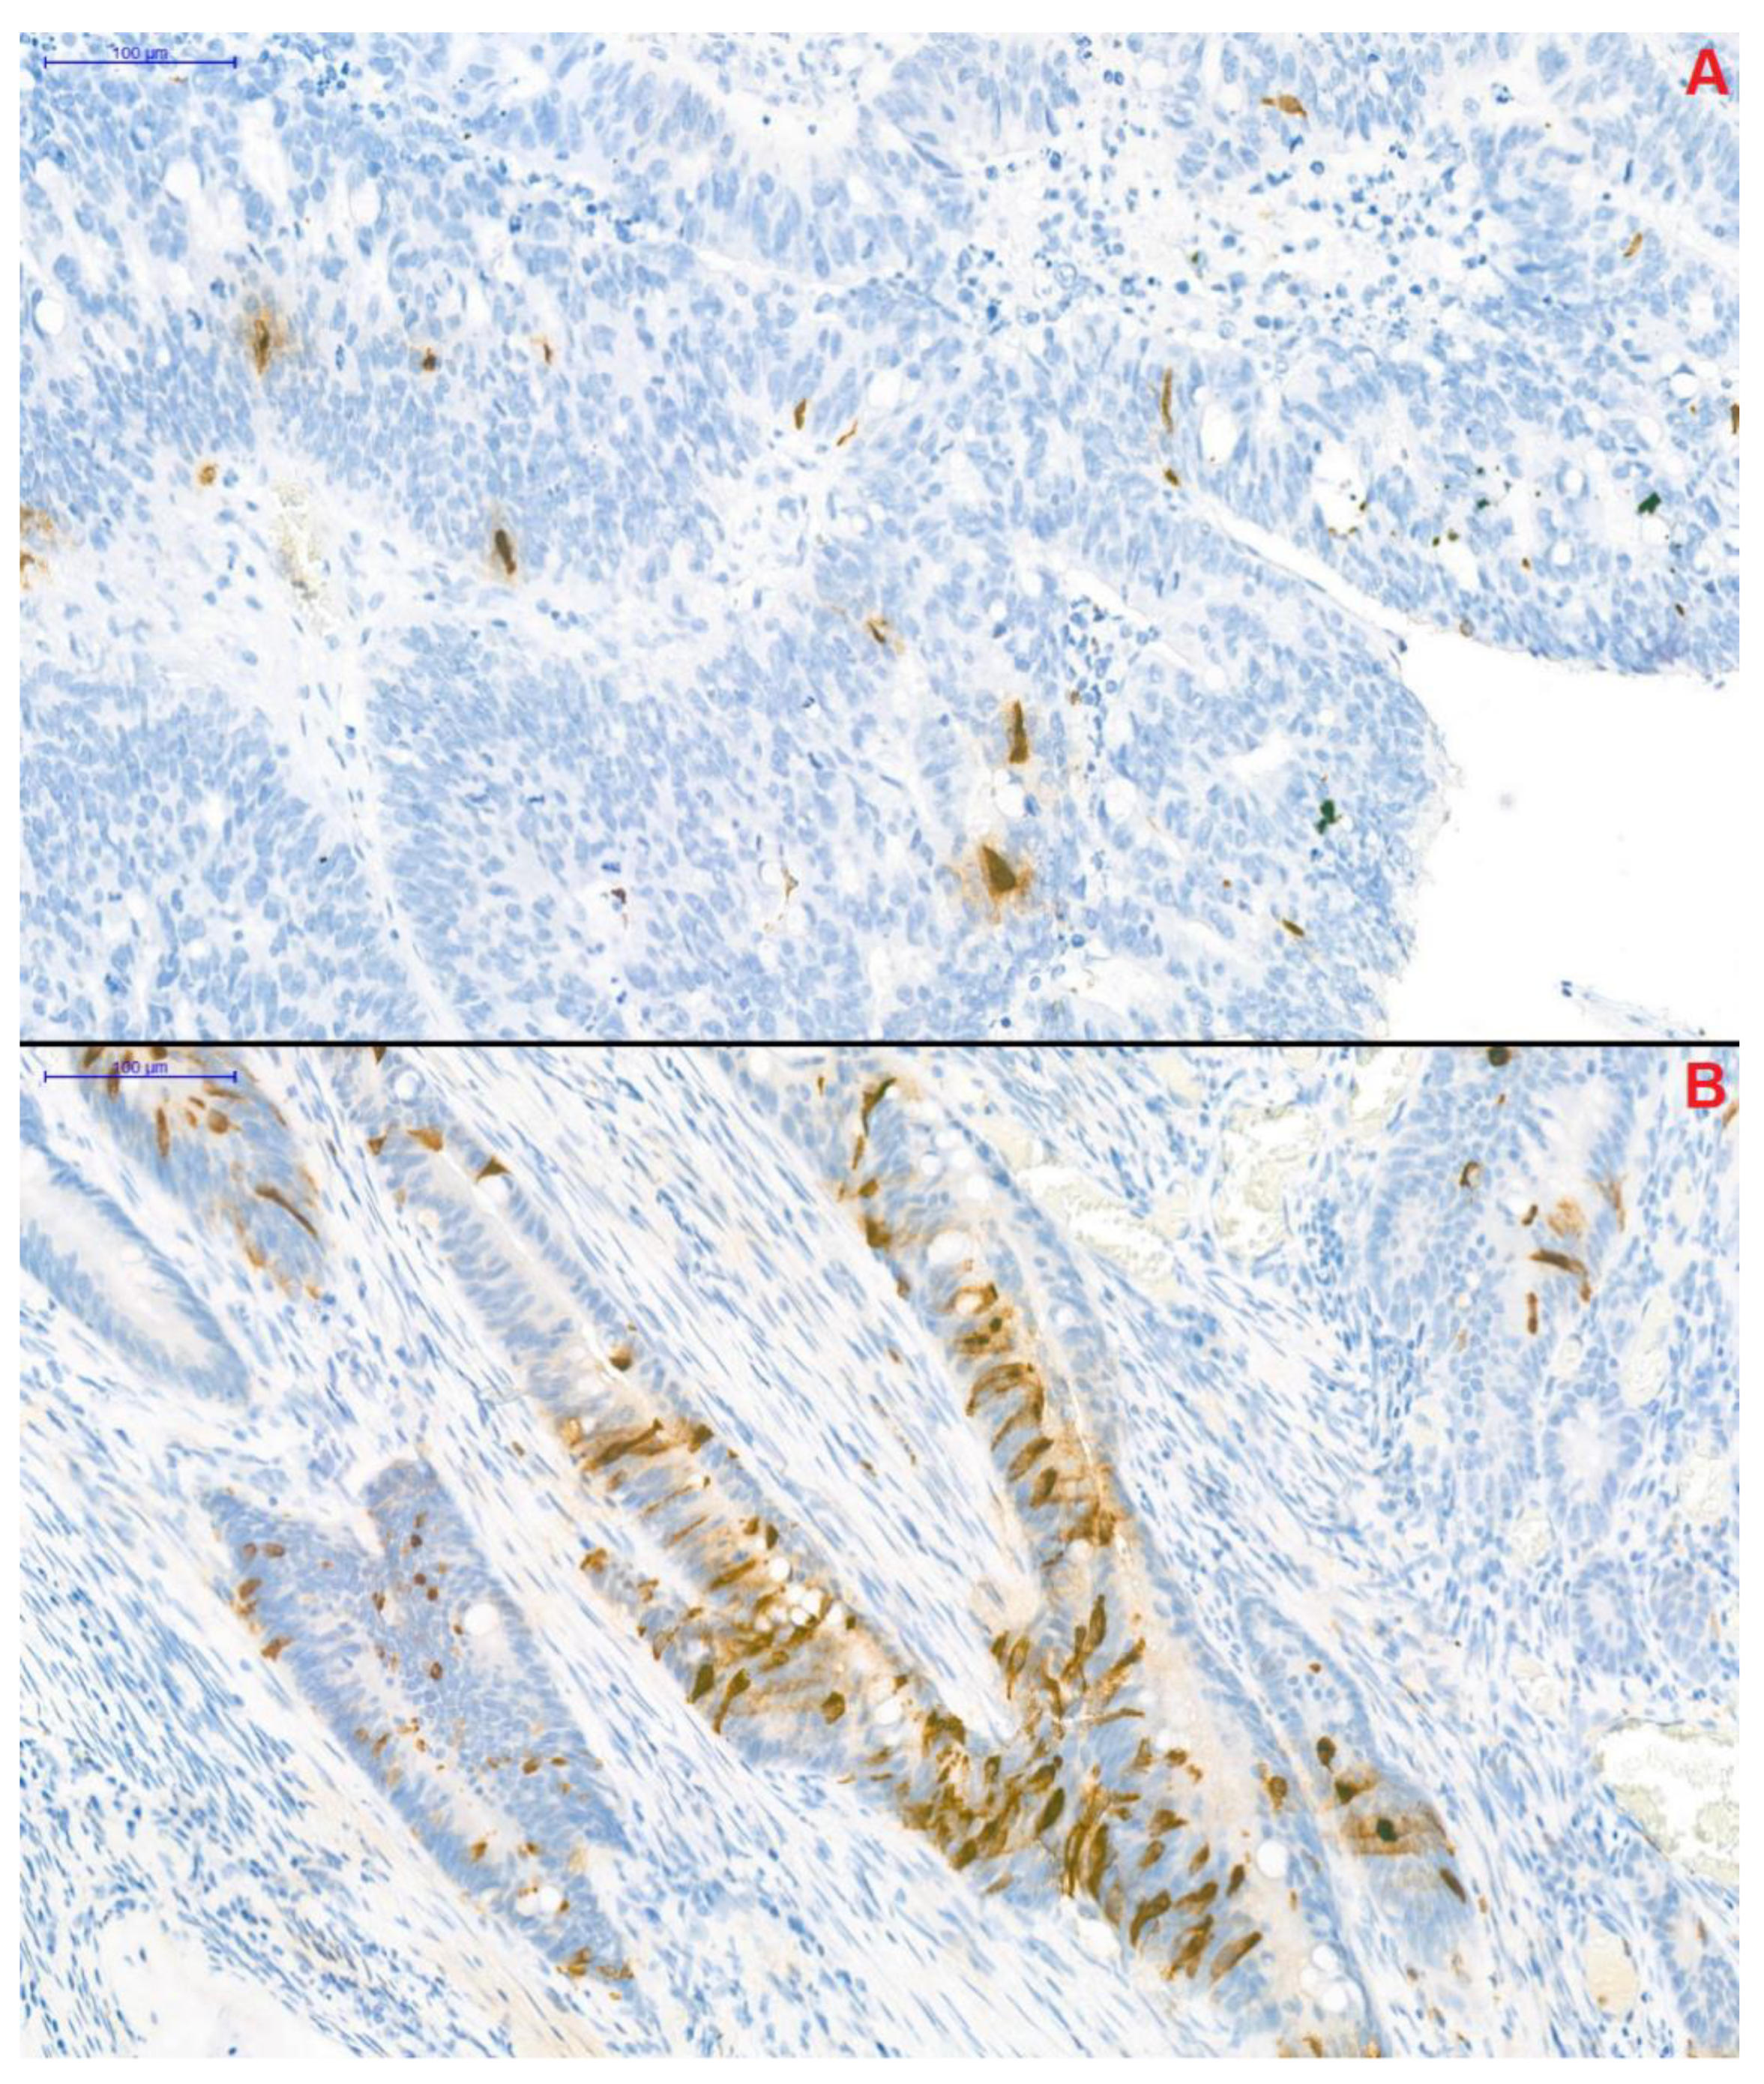

CgA-specific immunohistochemical staining of resected tumor segments was carried out with the Clone DAK-A3 Monoclonal Mouse Anti-Human Chromogranin A kit (M0869, dilution 1:1000; Dako Denmark A/S, Glostrup, Denmark). CgA-positivity was defined as previously described by Gulubova and Vlaykova [12]. Adenocarcinoma samples, in which anti-CgA-stained cells infiltrated beyond the muscularis mucosae were defined as CgA-positive. Two well-distinguishable patterns were observed: (1) CgA-positive cells were located randomly and individually or (2) the presence of a grouped pattern was observed in the remaining samples (Figure 3). Samples were blind-examined—the pathologist performing the immunohistochemistry was unaware of clinical and survival data of patients.

Figure 3.

Chromogranin A-specific immunohistochemical staining of colorectal cancer samples (magnification: 20×). Two distinguishable pattern of the chromogranin A-positive neuroendocrine (CgA+) cells could have been observed within the samples. In the first, CgA+ cells were located individually in a scattered pattern (A), while in the remaining samples CgA+ cells formed small groups (B).